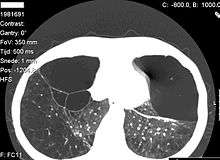

Emphysema due to alpha-1-antitrypsin deficiency.

Computed tomography of the lung showing emphysema and bullae in the lower lung lobes of a subject with type ZZ alpha-1-antitrypsin deficiency. There is also increased lung density in areas with compression of lung tissue by the bullae.